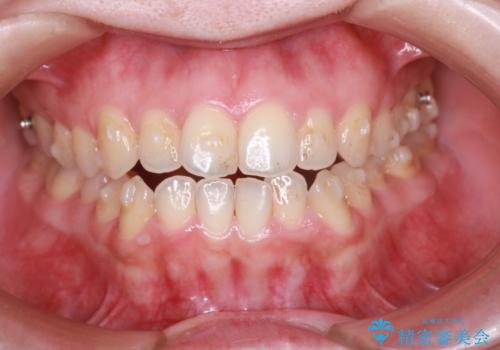

【オープンバイト】前歯のがたがたをなおしたい。

- 笑った時の前歯の見た目が気になることを主訴に来院されました。

上の歯が下の前歯を少し隠すぐらいを目指し、インビザラインにて治療を行いました。